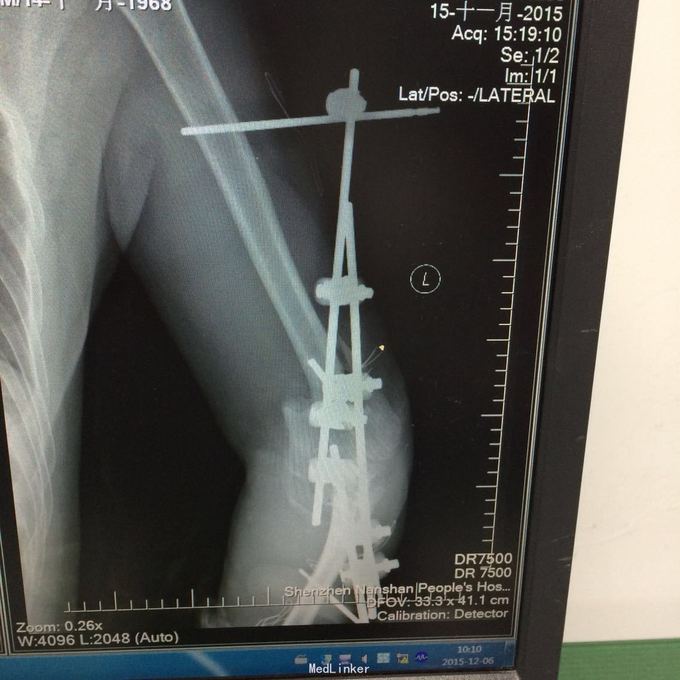

1、左肱骨远端粉碎性开放性骨折;2、左肘关节半脱位;3、左手第4、5掌骨远端骨折;4、右手第1、3、4远节指骨骨折;5、右手第5中节、远节指骨骨折;6、鼻部软组织挫裂伤;鼻中隔骨折;7、右侧第3--7肋骨折;8、左跟骨粉碎性骨折;9、左眉弓软质挫裂伤;10、左肺挫伤;11、脑震荡。 1.完善三大常规、PT四项、生化等各项常规检查; 2.完善CT检查,予抗破伤风、抗感染、镇痛、止血等对症支持治疗; 3.请口腔、耳鼻喉、眼科等相关科室会诊; 4.请示上级医师,指导下步治疗。 手术时间:2015年11月15日 术后诊断:左肱骨远端开放性粉碎性骨折 麻醉方式:全身麻醉 手术名称:左肱骨远端开放性粉碎性骨折清创缝合外固定架固定术 手术时间:2015年12月25日 术后诊断:左肱骨远端粉碎性骨折 麻醉方式:臂丛麻醉 手术名称:左肱骨远端粉碎性骨折切开复位内固定术 。 手术时间:2015-12-3 术后诊断:左跟骨粉碎性骨折;左肱骨远端粉碎性开放性骨折;左肘关节半脱位;左手第4、5掌骨远端骨折;右手第1、3、4远节指骨骨折;右手第5中节、远节指骨骨折;右足拇趾撕脱骨折并趾间关节脱位;鼻部软组织挫裂伤;鼻中隔骨折;右侧第3--7肋骨折;左眉弓挫裂伤;左肺挫伤;脑震荡。 麻醉方式:腰硬联合 手术名称:左跟骨粉碎性骨折切开复位钛板内固定术